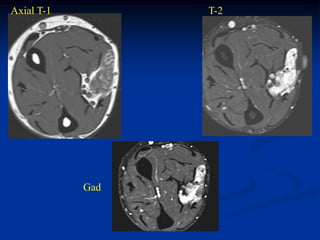

Case #270.2 Axial T-1 T-2 Gad 56 year male with painless soft mass in anterior thigh for 2 years

Axial T-1 T-2 fluid tumor Gad

• 263.

Sag T-2 Surgical specimen